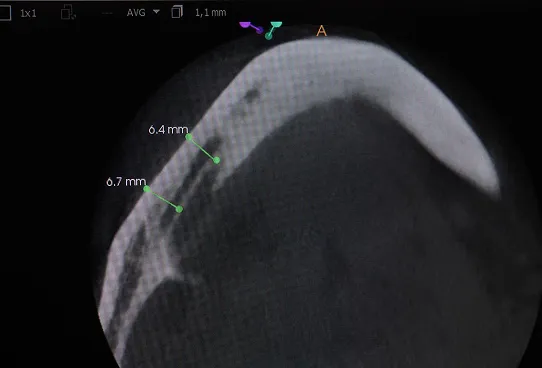

TRÓJWYMIAROWA REKONSTRUKCJA WYROSTKA ZĘBODOŁOWEGO PRZY UŻYCIU INDYWIDUALNIE DRUKOWANYCH SIATEK TYTANOWYCH YXOSS ReOss

To kolejna metoda umożliwiająca precyzyjną odbudowę zadanego kształtu tkanki kostnej przy użyciu standardowych materiałów kościotwórczych, kości własnej lub PRF oraz zewnętrznego rusztowania w postaci siatki z biozgodnego stopu tytanu. Siatka jest indywidualnie projektowana w technologii CAD CAM i następnie drukowana dla konkretnego przypadku.

Dotychczas stosowane stabilizatory zewnętrzne w formie siatek tytanowych używane do regeneracji kostnej lub w zabiegach odtwórczych w chirurgii szczękowo-twarzowej uwzględniały materiały ręcznie doginane i formowane podczas zabiegu operacyjnego. Zastosowanie technologii CAD CAM dla potrzeb druku materiałów przeznaczonych do indywidualnej rekonstrukcji kostnej znacznie poprawiło precyzję i jakość uzyskiwanych efektów. Wdrożenie biozgodnych stopów tytanu do druku siatek zdecydowanie ograniczyło odsetek powikłań zapalnych.

Precyzja projektu druku siatki bazuje na dokładności odwzorowania kształtu kości w stożkowej tomografii komputerowej CBCT, co zapewnia ich dobre przyleganie do podłoża kostnego oraz ogranicza powstawanie powikłań w postaci obnażania się siatek. Precyzja projektu oraz materiał, z którego wykonana jest siatka (biozgodny stop tytanu), powodują, że obnażenie się siatki nie zaburza procesu gojenia i regeneracji kostnej.

Wymaga jedynie większej ilości kontroli pozabiegowych oraz wzmaga czujność higieniczną zarówno ze strony lekarza, jak i pacjenta. Ten rodzaj odbudowy kostnej stosowany jest w sytuacjach złożonych, trójwymiarowych 3D ubytków kości, przy których standardowe metody odbudowy są niewystarczające. Ilość kości, którą możemy uzyskać, stosując tę metodę, to nawet kilka centymetrów sześciennych.

Metoda rekonstrukcji kostnej w oparciu o indywidualnie drukowane siatki z tytanu dla implantacji wszczepów śródkostnych stosowana jest najczęściej jako dwuetapowa. W pierwszym etapie odbudowywana jest kość, natomiast implanty wszczepiane są po okresie 4–6 miesięcy. Na wgojenie implantów oczekujemy od 4 do 6 miesięcy w zależności od miejsca ich lokalizacji. Siatka tytanowa po spełnieniu swojej funkcji rusztowania dla odbudowującej się kości jest następnie usuwana w dniu wszczepienia implantu. Jeżeli kość spełnia odpowiednie warunki, istnieje możliwość zastosowania modyfikacji siatki tytanowej, która umożliwia jednoczesne wprowadzenie implantów wraz z odbudową kostną.